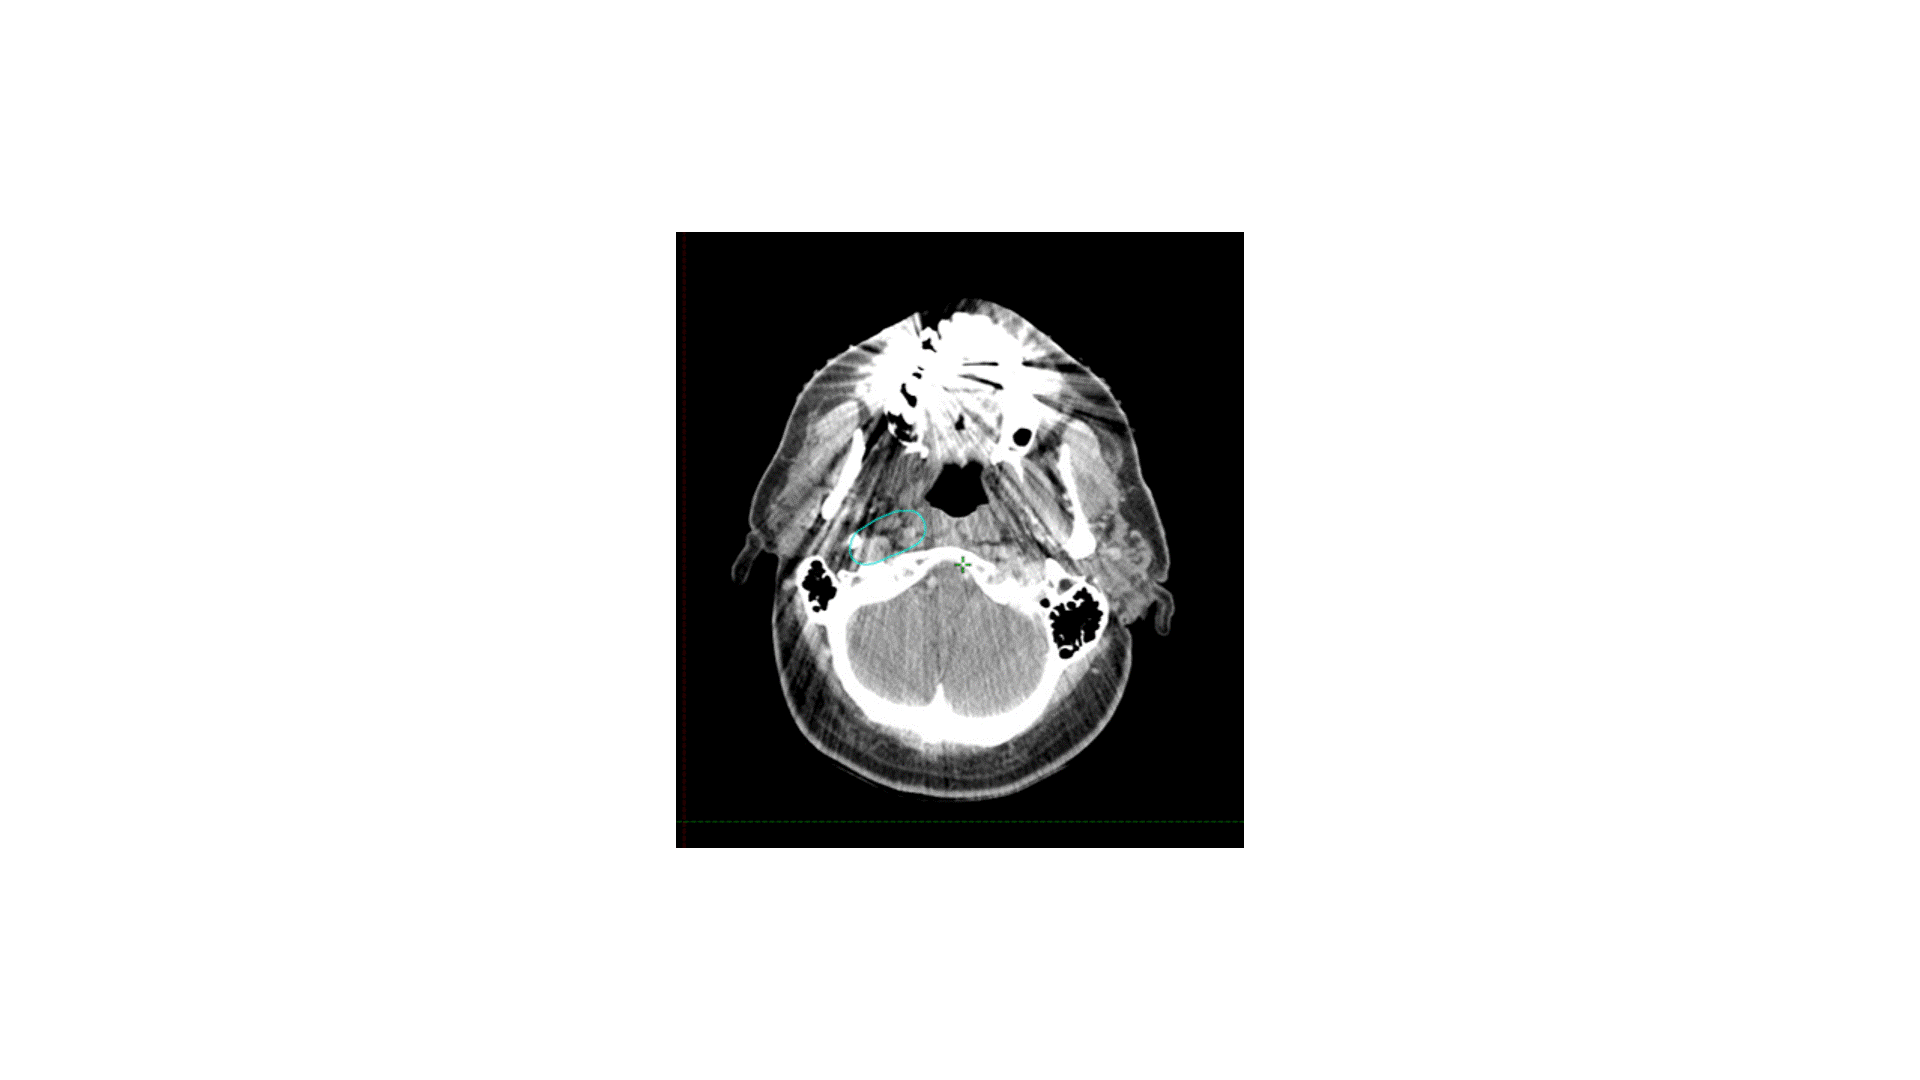

A 70-year-old man with no smoking history presented with a right neck mass. FDG PET showed uptake in the tonsil and the neck at level II. Fine needle aspiration of the neck mass revealed p16+ squamous cell carcinoma (SCCA). He underwent transoral robotic surgery; intra-operative exam showed minimal base of tongue involvement and no soft palate invasion. Pathology after tonsillectomy and ipsilateral neck dissection revealed a 3 cm SCCA primary tumor, closest margin 3 mm, without perineural invasion or lymphovascular space invasion. The level II node was 4 cm without extranodal extension, pT2N1.

The indication for adjuvant radiation in this case was a lymph node > 3 cm. The primary was T2 without PNI or LVSI and 3 mm margins, so I did not specifically target the primary, though I did include some clips. The treatment I chose for this patient was option B, treating the right level II-V (56 Gy) plus the retrostyloid and lateral retropharyngeal lymph nodes (50 Gy). Chemotherapy was not indicated. Simply treating II-V would not have been adequate, as oropharyngeal primaries do drain to the retropharyngeal lymph nodes, and failure there can be catastrophic. Furthermore, with a 4 cm ipsilateral lymph node in level II, there is risk of retrograde drainage to the retropharyngeal region.

How I do it: defining retropharyngeal nodes at risk

Remember that there are lateral and medial retropharyngeal lymph nodes (RPLNs). When there is pathologic involvement of RPLNs, it is almost always the lateral RPLN that is involved first. Note that the lateral RPLN space is the fat space (dark on CT) immediately medial to the internal carotid artery.

When electively treating the retrostyloid and RPLN as in this case, I usually only treat the lateral RPLN. If the RPLN was grossly involved with cancer, I would include both the lateral and medial RPLNs.